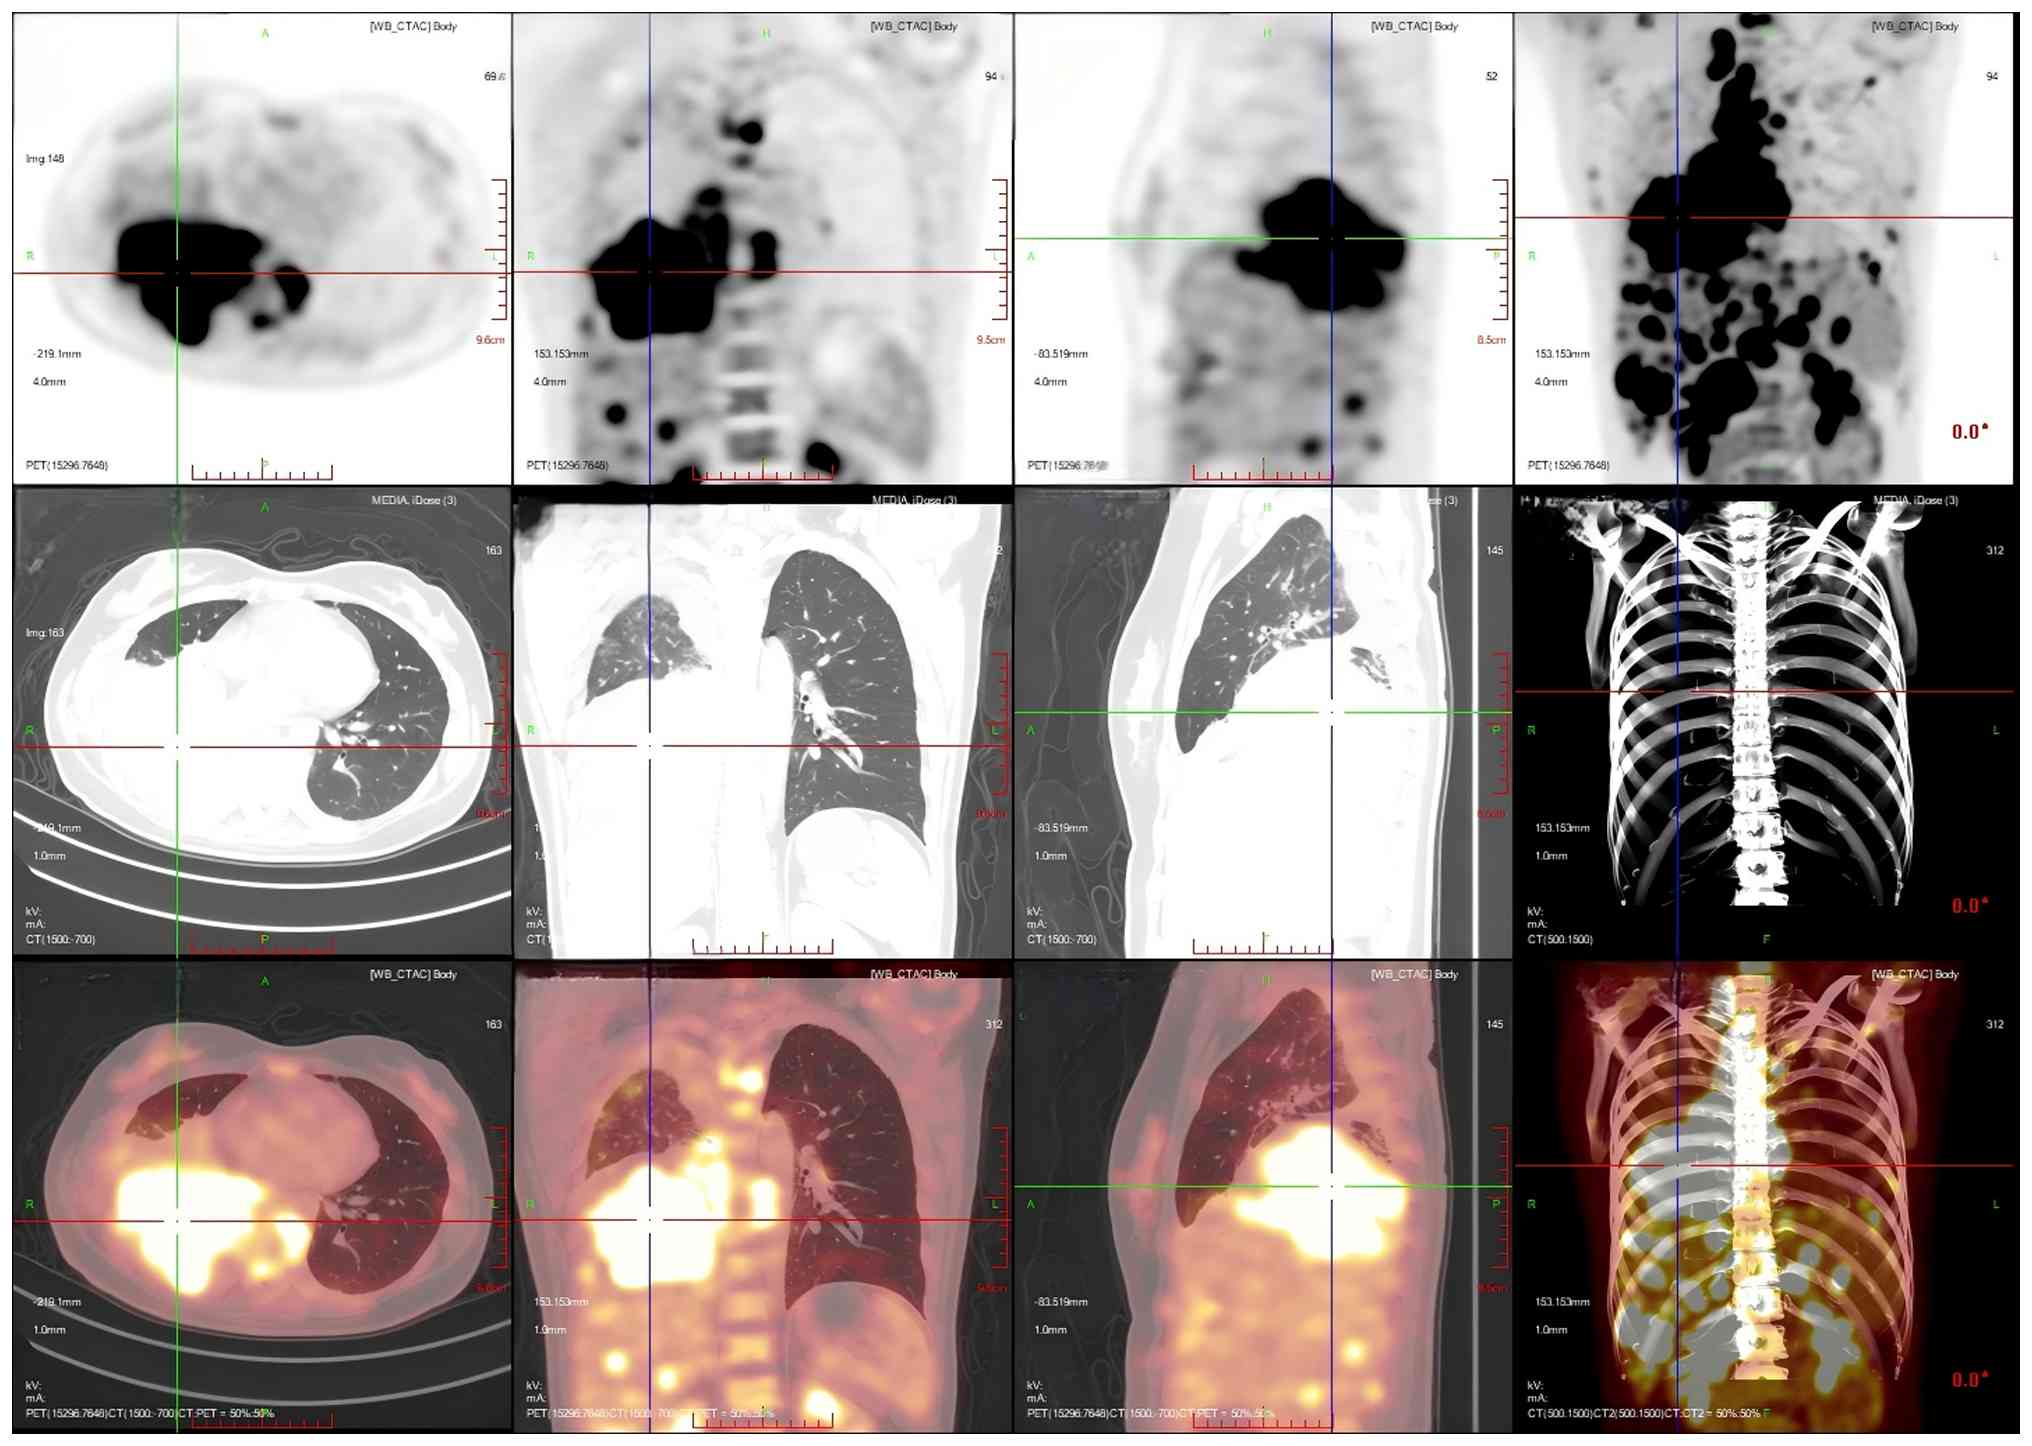

After 1 month, the patient developed numbness and discomfort below the waist, weakness of both lower limbs and limitations to lifting. To clarify the changes in the condition of the patient, positron emission tomography/CT (PET/CT) was performed. PET/CT images showed that an irregular mass-like hyperdense shadow was detected in the right lung hilar and the middle and lower lobes of the right lung; no normal lung tissue was seen, the lesion crossed the interlobular pleura and invaded the upper lobe of the right lung, and the corresponding area on PET showed a mass-like radiolucency focus with an maximum standardized uptake value (SUVmax) of 25.8 (Fig. 5). Multiple enlarged and swollen lymph nodes were detected in the mediastinum, bilateral pulmonary hilar region, bilateral diaphragmatic pedicle and right cardiogenic angle area, partially fused in the form of a mass. PET showed a mass of radiolucent foci in the corresponding areas, and the SUVmax of the hypermetabolic area under the bronchus was measured to be 21.4. Thickening of the right pleura was observed, an arcuate fluid density shadow was seen in the thoracic cavity and mild radiolucent uptake was visible in the area of pleural effusion on the right side of the chest cavity (Fig. 6). The liver was full, with diffuse low-density nodules and masses of varying sizes within it, and PET showed nodular and mass-like radioactivity uptake in the corresponding areas. The low-density mass in the S4 segment of the liver was measured to be ~5.0×4.4 cm in size, with an SUVmax of 20.0. Several enlarged lymph nodes were observed in the portal region of the liver, which had fused to form a mass. PET scans showed mass-like radioactivity uptake in the corresponding areas, with a SUVmax of 20.2 (Fig. 7). Multiple nodular and striated radiographic uptake of the right humeral head, multiple parts of the sternum, bilateral scapulae, cervical, thoracic and lumbar vertebral bodies, part of the accessory bones, the two flanks of the sacrum, multiple parts of the pelvic bone and the proximal segment of the left femur were noted. CT demonstrated an inhomogeneous increase in the density of the bone at the corresponding sites, discontinuity of the cortex in some of the neighboring bones, flattening of the seventh thoracic vertebral body, morphological disorders and an increase in the peripheral soft-tissue shadows. A high metabolic area was measured in the seventh thoracic vertebral body, with an SUVmax of 20.4 (Fig. 8).

Multiplanar 18F-FDG PET/CT imaging of

the patient's hilar hypermetabolic confluent lymph nodes. The liver

was full, with diffuse low-density nodules and masses of varying

sizes in the liver, and PET showed nodular and mass-like

radioactivity uptake in the corresponding areas. The low-density

mass in the S4 segment of the liver was measured to be ~5.0×4.4 cm

in size, with a SUVmax value of 20.0. Several enlarged

lymph nodes were observed in the portal region of the liver, which

had fused to form a mass. PET scans showed mass-like radioactivity

uptake in the corresponding areas, with a SUVmax value

of 20.2. Imaging modalities: PET (top row); CT (middle row); PET/CT

fusion imaging (bottom row). Imaging planes: Axial Plane (first

column): Cross-sectional views depicting transaxial details of the

hepatic hilar coalescent lymph nodes. Coronal plane (second column)

showing frontal views, illustrating the craniocaudal distribution

of the hepatic hilar lesions. Sagittal plane (third column):

Lateral views showing anteroposterior localization of the

hypermetabolic lymphadenopathy in the hepatic hilum.

Volume-rendered CT (fourth column, middle row): 3D reconstructed

whole-body CT, visualizing the spatial relationship between the

hepatic hilar lesions and thoracic/pelvic bony structures. CT,

computed tomography; PET, positron emission tomography.

Figure 7.

Multiplanar 18F-FDG PET/CT imaging of the patient's hilar hypermetabolic confluent lymph nodes. The liver was full, with diffuse low-density nodules and masses of varying sizes in the liver, and PET showed nodular and mass-like radioactivity uptake in the corresponding areas. The low-density mass in the S4 segment of the liver was measured to be ~5.0×4.4 cm in size, with a SUVmax value of 20.0. Several enlarged lymph nodes were observed in the portal region of the liver, which had fused to form a mass. PET scans showed mass-like radioactivity uptake in the corresponding areas, with a SUVmax value of 20.2. Imaging modalities: PET (top row); CT (middle row); PET/CT fusion imaging (bottom row). Imaging planes: Axial Plane (first column): Cross-sectional views depicting transaxial details of the hepatic hilar coalescent lymph nodes. Coronal plane (second column) showing frontal views, illustrating the craniocaudal distribution of the hepatic hilar lesions. Sagittal plane (third column): Lateral views showing anteroposterior localization of the hypermetabolic lymphadenopathy in the hepatic hilum. Volume-rendered CT (fourth column, middle row): 3D reconstructed whole-body CT, visualizing the spatial relationship between the hepatic hilar lesions and thoracic/pelvic bony structures. CT, computed tomography; PET, positron emission tomography.